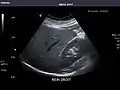

Right kidney

Kidneys: Right and left kidneys measure 11.5 cm and 12 cm in length respectively. No hydronephrosis. Small left lower pole kidney cyst.